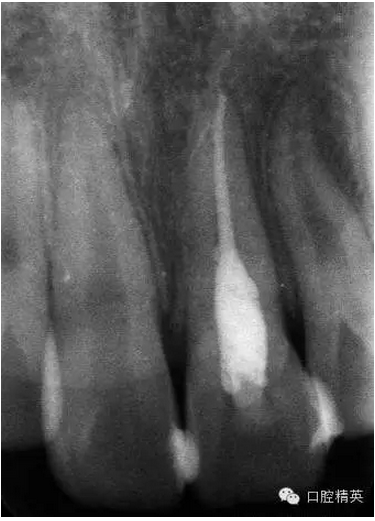

x線檢查:21牙槽窩空虛,窩內(nèi)未見(jiàn)其他遺留物。

圖3.患者21根尖片,牙槽窩空虛,無(wú)變形。